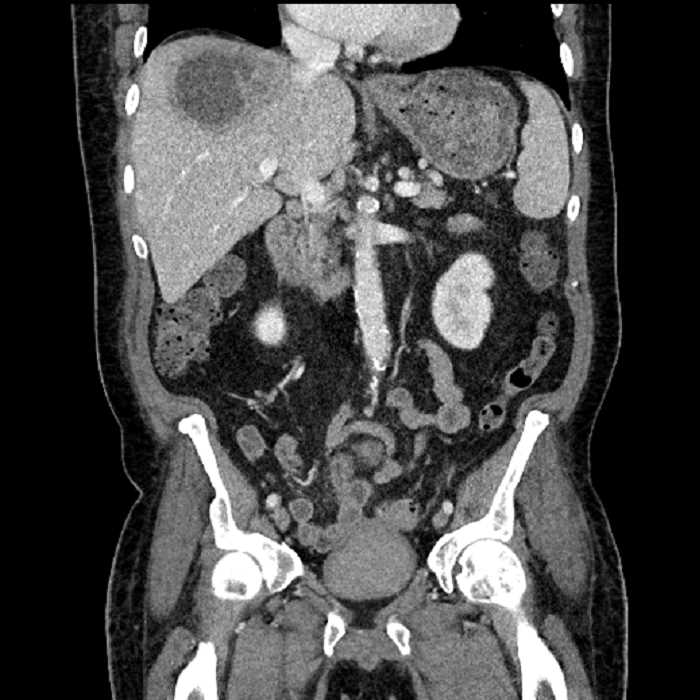

Age: 63

Sex: Male

Indication: Abdominal pain

• Large fluid density structure in hepatic segments 7 and 8 measuring 10 x 7 x 7 cm with internal septation and circumferential ill-defined low density compatible with edema

• Peripherally enhancing subcapsular collections along the anterior margin of the left hepatic lobe measuring 3 x 1 cm and 2 x 1 cm

• Clearly marginated fluid density structure in segment 7 and several other scattered tiny hypodensities, which likely represent cysts

• High grade stenosis of the left common iliac artery, with the left internal and external iliac arteries remaining patent

• Hepatic abscess

Acute sigmoid diverticulitis complicated by a small contained perforation and a large abscess in the right hepatic lobe. Additional small subcapsular abscesses along the anterior margin of the left hepatic lobe.

Additionally, loss of the normal fat plane between the peridiverticular collection and adjacent thickened loops of small bowel raises the potential for an enterocolonic fistula.

• The classic CT imaging appearance is a double target sign with internal low density surrounded by an internal enhancing rim (capsule) and a low density external rim (edema)

Hepatic abscess showing the double target sign with low density internally surrounded by a thin inner enhancing rim (red arrow) and ill-defined outer low density rim (yellow arrow). Blue arrow indicates an internal septation. Red arrows: additional smaller subcapsular abscesses. Red arrow: focal contained perforation associated with diverticulitis.